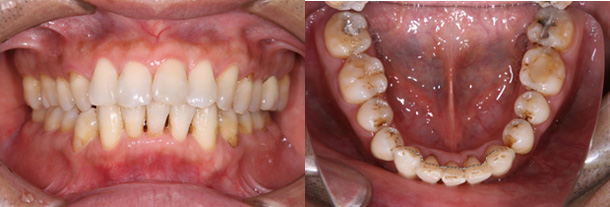

症例:上顎前歯のすき間を改善

主訴:上の前歯のすきっ歯が気になる

診断:上顎の正中離開

年齢:22歳

装置:上顎部分的ブラケット装置

治療期間:5か月

抜歯:なし

費用:100,000円+税

矯正前

矯正中

矯正後